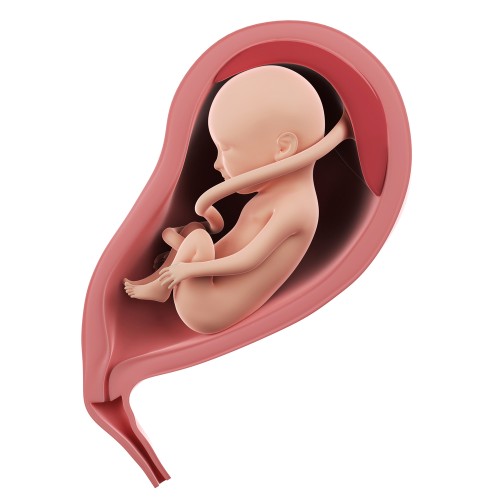

На 27-й неделе беременности ребенок уже выглядит как новорожденный. Все его части тела гармонично развиты: на голове появляются волосы, а на лице заметны брови и ресницы. К началу третьего триместра многие малыши принимают правильное головное положение, что считается нормой. Тазовое предлежание — это патология, которая может усложнить роды. Если врач обнаруживает такое положение плода, он может рекомендовать будущей маме специальные упражнения.

Рост плода от макушки до пяток составляет примерно 34 см. По своим размерам малыш напоминает кочан цветной капусты. На этом этапе продолжается активное развитие всех внутренних органов и систем, что готовит ребенка к самостоятельной жизни вне материнской утробы.

Также происходит значительное увеличение массы малыша. Вес ребенка на 27-й неделе беременности составляет около 1 кг.

Плод на 27 неделе

Основной этап роста ребенка практически завершен. Теперь его органы и системы начинают улучшаться и готовиться к жизни вне материнского организма.

На 27-й неделе беременности происходит важный этап в развитии коры головного мозга: активизируются нейронные связи. В этот период улучшается иммунная система плода, что позволяет ему реагировать на аллергены, поступающие через плаценту. Поэтому будущей маме следует внимательно подбирать свой рацион.

Кожа малыша становится более гладкой благодаря увеличению подкожно-жировой клетчатки. В организме ребенка начинает функционировать собственный обмен веществ, что может привести к снижению аппетита у многих женщин.

Эндокринная система плода начинает активно работать: щитовидная и поджелудочная железы вырабатывают гормоны, и с каждым днем малыш становится менее зависимым от гормонального фона матери. Женщина может заметить улучшение своего самочувствия в связи с этим.

Развитие плода на 27-й неделе затрагивает и дыхательную систему. В легких находится амниотическая жидкость, которая позволяет им растягиваться и увеличиваться в объеме. В пузырьках на концах бронхиол продолжается выработка сурфактанта, который предотвращает слипание легочных альвеол и защищает от инфекций.

Дыхание ребенка в утробе осуществляется через плаценту, но он уже способен выполнять дыхательные движения благодаря рефлексам, совершая около 40 движений в минуту. Кислород крайне важен для развития и нормального функционирования внутренних органов, особенно сердца, и его нехватка может привести к гипоксии. Одним из признаков этого состояния являются учащенные движения плода.